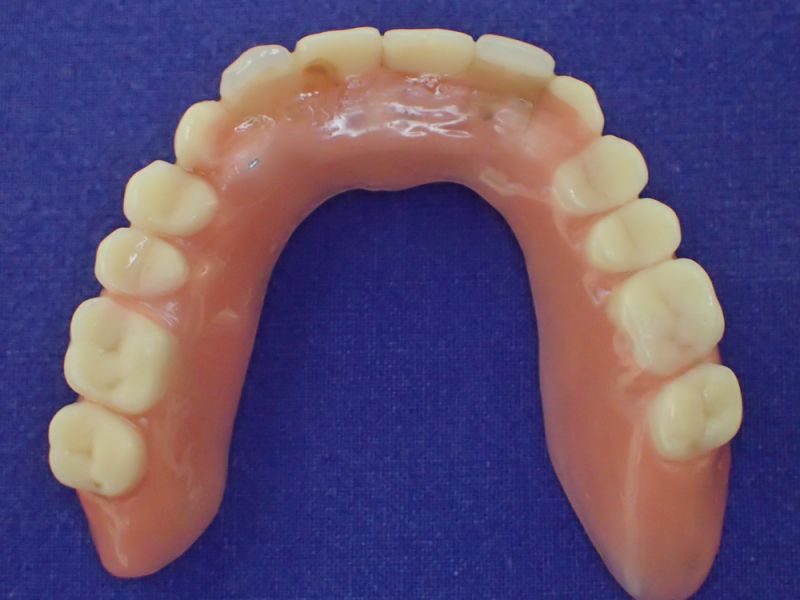

2007 wurde diese implantatgestützte Versorgung erstellt. Die 8 Implantate wurden allesamt hier inseriert und befinden sich bis heute, vollkommen unverändert in Funktion.

Nach inzwischen 12 jähriger Tragedauer wurden alle Kunststoffteile erneuert, das metallische Grundgeroüst der Arbeit erhalten und die Arbeit befindet sich in einem Zustand, der sich weitgehend an der Ersterstellung orientiert.

Bei derartigen Arbeiten ist es tatsächlich möglich grundlegende Konstruktionsmerkmale einer alten Arbeit zu übernehmen und Verschleißteile aus Kunststoff zu erneuern.

Im Prinzip ist das beliebig oft möglich und für den Patienten mit einer enormen Kostenersparnis verbunden.